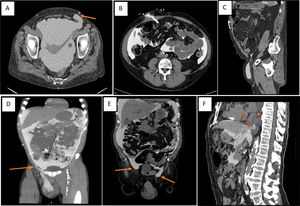

Two of the abdominal lumps were identified as hernias (Fig. 1A), another was identified as dialysate leakage through the catheter entry point (Fig. 1B), and in the fourth case, the leakage point was not visualized. Cases of genital edema were identified as dialysate leakage on 3 occasions (Fig. 1C and D) and as inguinal hernias on the fourth (Fig. 1E). In one of the ultrafiltration defect cases, a dialysate leak point could not be confirmed, and in the other, a pleuroperitoneal communication was demonstrated (Fig. 1F).

A: Abdominal bulge due to hernia (arrow). B: Leakage of dialysate through the subcutaneous route. C: Dialysate leakage due to persistence of the duct processus vaginalis. D: Leakage of the dialysate by dissection of planes from a small point of leakage (arrow). E: Genital edema due to bilateral hernias (arrows). F: Ultrafiltration failure due to peritoneal pleural leakage (arrow = vanishing point) (star = pleural effusion).